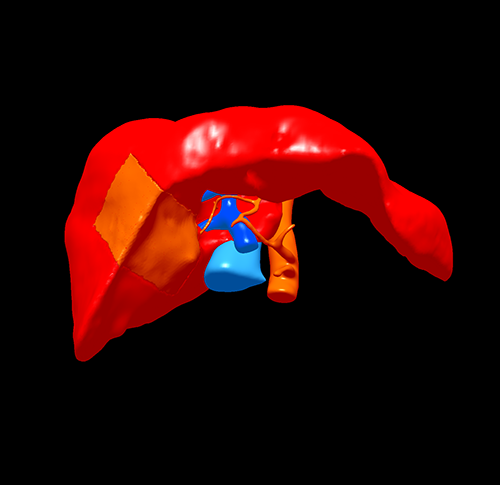

S5 肝癌--腹腔镜S5切除